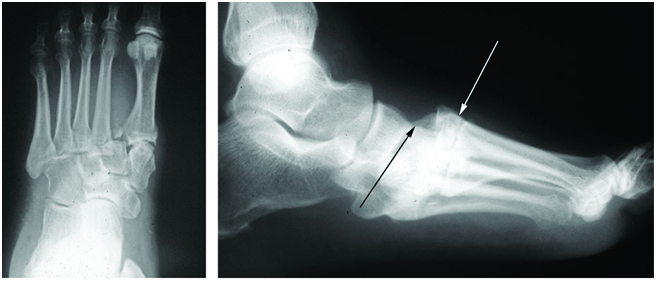

In weight bearing anteroposterior radiographs, the medial border of the second metatarsal base should be co-linear with the medial border of the intermediate cuneiform when the joint is uninjured (figure 2). In some cases, malalignment is obvious in the radiography (figure 3). Adequate anteroposterior radiographs must show a tangential view of the second tarsometatarsal joint (figure 1, right) since views oblique to the joint may miss subtle displacements (figure 1, middle). Radiographs may show a small bony avulsion type fracture between the first and second tarsometatarsal joints (figure 3, left) (Myerson et al., 1986).

Figure 3: Widely displaced Lisfranc injury. Left: Anteroposterior view showing lateral displacement of the Lisfranc articulations. Right: Lateral view showing the dorsal displacement of the metatarsals (white arrow) relative to the mid-foot (black arrow).